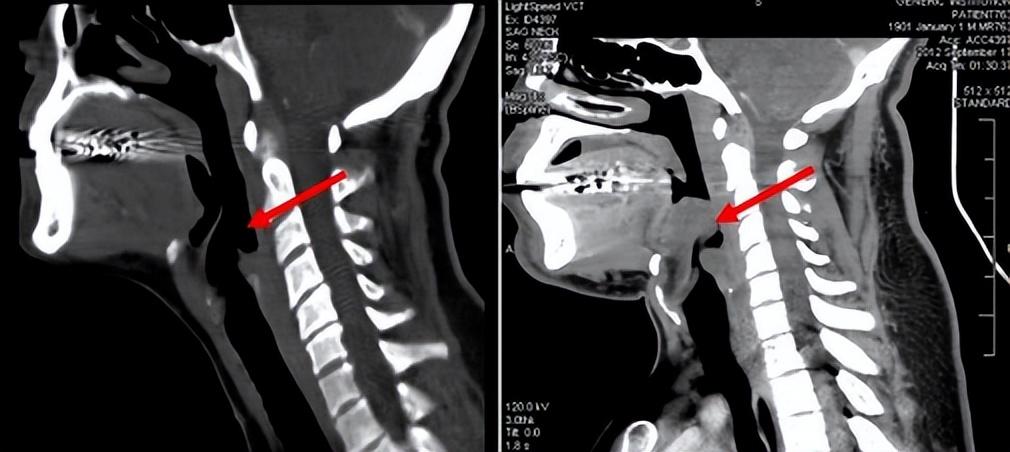

因為病人在入院前就有明顯的咽喉部疼痛,後來癥狀加重出現了吞咽困難,再後來呼吸困難,甚至還出現了憋氣感,還伴隨著畏寒癥狀,這一切都指向了無比兇險的急性會厭炎。加上後來檢查時,患者的會厭腫大明顯,喉嚨呈拇指征,更加肯定了這種猜想。